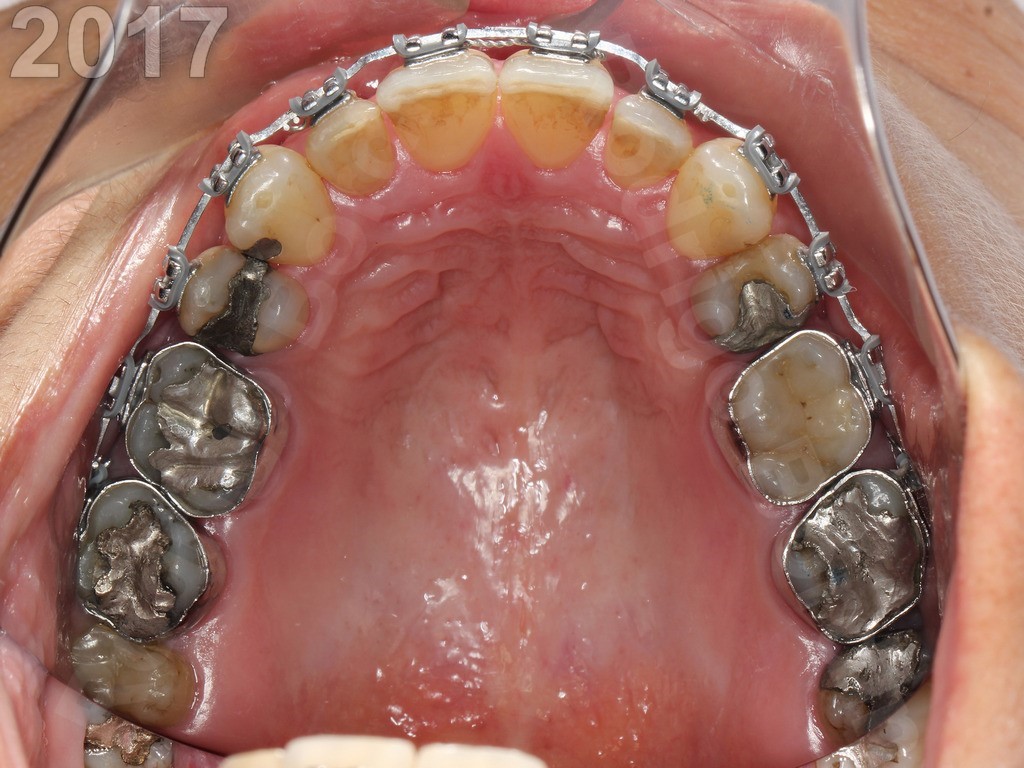

Após terminar o tratamento ortodôntico desta paciente, fiz o clareamento dentário e, uma a uma, substituí as antigas restaurações escuras de amálgama, esteticamente insatisfatórias, por restaurações em resina composta. Nenhuma coroa de porcelana foi necessária, neste caso. Note que mesmo em grandes destruições dentárias, desde que, se tomados devidos cuidados de planejamento, podem sim receber grandes restaurações em resina composta, sem a necessidade de se utilizar de coroas de porcelana, que exigem maior desgaste ainda do dente, que já se encontra bem fragilizado.